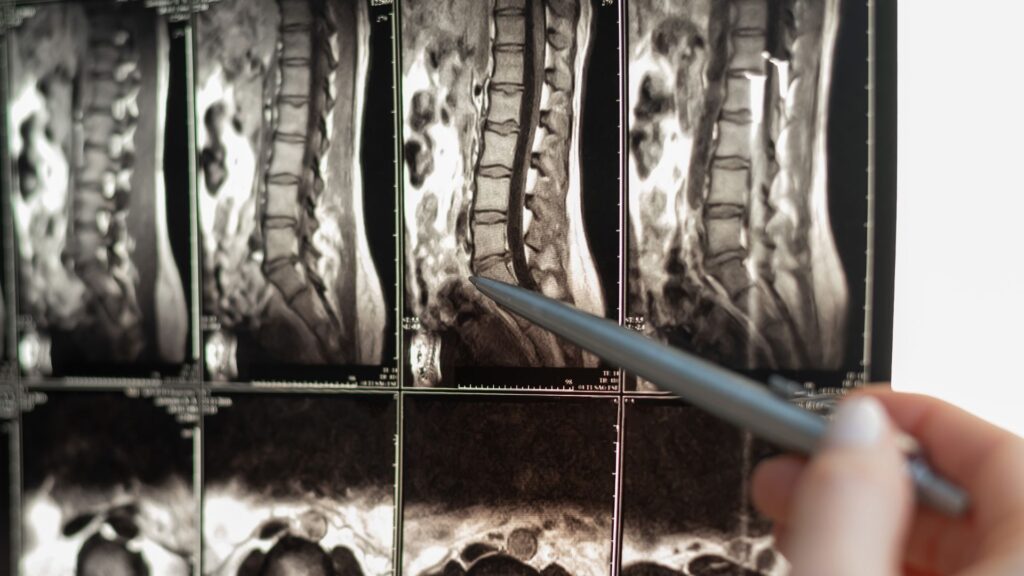

El Instituto Nacional de Trastornos Neurológicos y Apoplejía (NINDS por sus siglas en inglés) define una lesión de médula espinal (LME) como un daño al grupo de nervios y fibras nerviosas que envía y recibe señales desde el cerebro. Una LME puede ser causada por una lesión directa a la misma médula espinal o por daño al tejido y huesos (vértebras) que rodean la médula espinal.

La severidad y magnitud de una LME varía dependiendo del tipo de daño y accidente en el cual una persona ha estado involucrada, aunque la probabilidad de sufrir daños temporales o permanentes es significativamente alta. Ya que una LME puede afectar la sensibilidad, fuerza y funcionalidad del cuerpo humano, todas las LME pueden ser clasificadas en una o dos categorías: Total y parcial.

Si bien la mayoría de lesiones medulares pueden ser clasificadas como total o parcial, adicionalmente son categorizadas basándose en cuál parte de la columna se lesiona. Cervical, torácica, lumbar y sacra son las 4 regiones de la columna que pueden lesionarse en un accidente y cada una tiene una función diferente en el cuerpo.